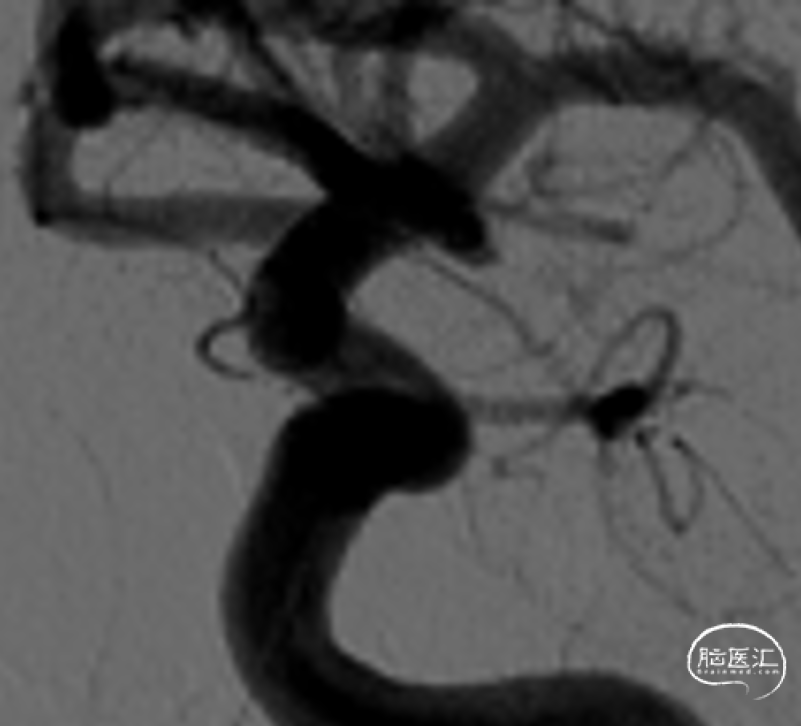

载瘤动脉近端直径4.24mm,远端直径3.05mm,选择通桥麒麟™血流导向密网支架 TQL-40-45。

微导丝囊内成绊,超选到大脑中动脉M1远端。

撤出微导丝,送入弹簧圈微导管至瘤腔内。

固定输送系统,回撤微导管,逐步释放通桥麒麟™血流导向密网支架头端,至头端张开为V型。

继续送入弹簧圈填塞。

再次造影确认打开情况,用微导丝继续按摩支架尾端。